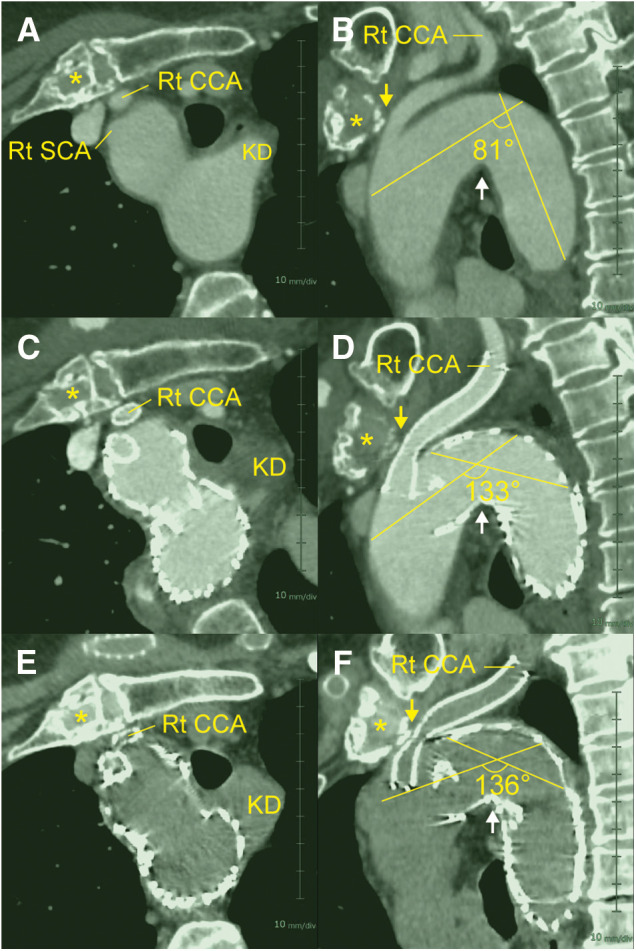

由于其独特的解剖特征,Kommerell憩室的血管内修复手术是一项挑战。一位 80 岁的无症状女性患者患有 Kommerell 憩室和相关的右侧主动脉弓,她接受了血管内修复术,包括主动脉弓近端延伸内膜移植术、腋窝-腋窝交叉旁路术和右锁骨下平行内膜移植术。由于完成主动脉造影后发现动脉闭塞,因此又在右颈动脉源头逆行放置了一个支架。随访 6 个月期间,她的状况良好,没有出现任何神经功能障碍。本报告阐明了导致右颈动脉骨膜闭塞的疾病特异性和手术相关原因。

Owing to the unique anatomical features, the endovascular repair for Kommerell diverticulum poses a surgical challenge. An 80-year-old, asymptomatic female with Kommerell diverticulum and associated right-sided aortic arch underwent an endovascular repair, consisting of an aortic arch endografting with a proximal extension, axillo-axillary crossover bypass, and right subclavian parallel endografting. An additional stent was promptly placed retrogradely at the right carotid artery origin as the completion aortography revealed an ostial occlusion. During the 6th month follow-up, she remained well without any neurological deficits. This report elucidated the disease-specific and procedure-related causes leading to right carotid artery ostium occlusion.